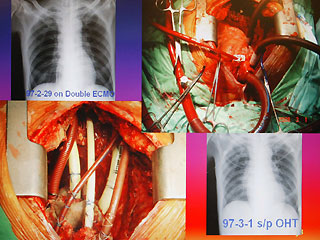

病人陳先生感染細菌性心內膜炎,造成心臟破壞(左下方),進行全心臟摘除術,并放置葉克膜(右上方)體外維生系統以維持生命。

中國臺灣網4月1日消息 據臺灣媒體報道,臺大醫院在病人沒有心臟狀態16天后,成功完成心臟移植,創全世界首例。

報道說,現年60歲的陳先生,2月初因發現感染細菌性心內膜炎,致使整顆心臟感染嚴重,從奇美醫院轉到臺大醫院之后,經家屬同意,決定進行全心臟摘除,然后置入葉克膜維持生命。陳先生最后靠著葉克膜撐過16天,奇跡式活下來,于今天順利出院。

臺大醫院心臟血管外科教授王水深率領團隊執行這個艱難的手術。他說,陳先生心臟的三尖瓣膜等處已被細菌噬光,無法修補,最后“走投無路”之下,決定先摘除心臟,而家屬的決定也需要相當大的勇氣。

王水深說,摘除心臟時沒人能保證有心臟可換,而靠葉克膜體外維生系統通常也只能維持7天左右,但陳先生靠著兩套葉克膜奇跡式的撐過16天,克服感染及排斥,又能幸運的等到心臟捐贈者,他強調,翻遍文獻可說史無前例。(周先)